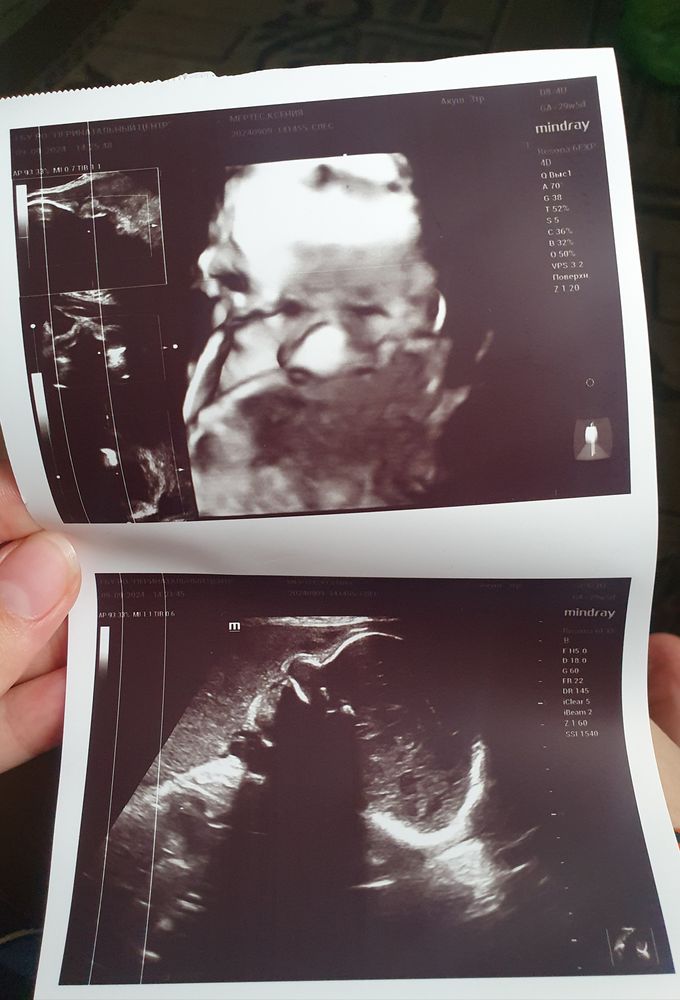

У моего был нос на весь экран, мы чуть не упали)) родился с маленьким Изображение